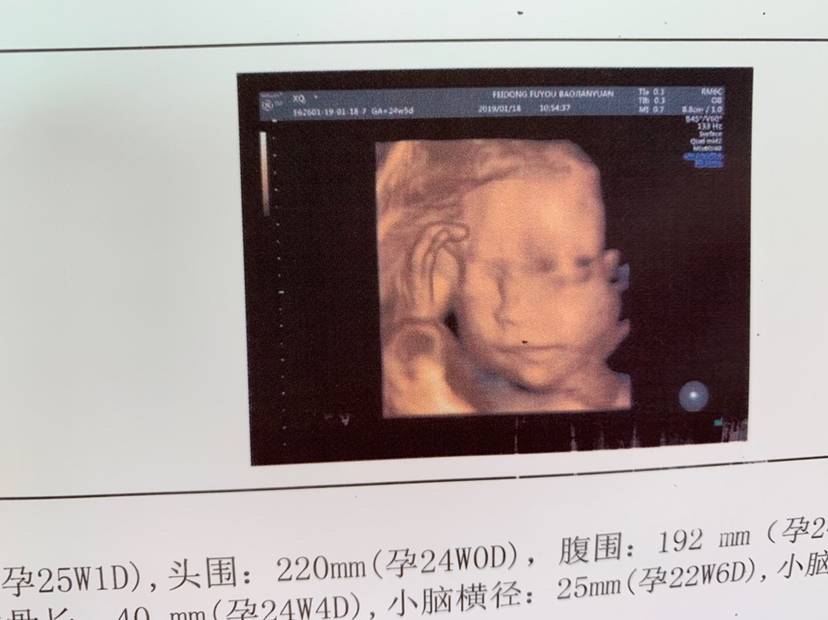

你家孩子四维看着好清秀~

辛辛😘[帖主]:是的哦😊医生护士都这么说